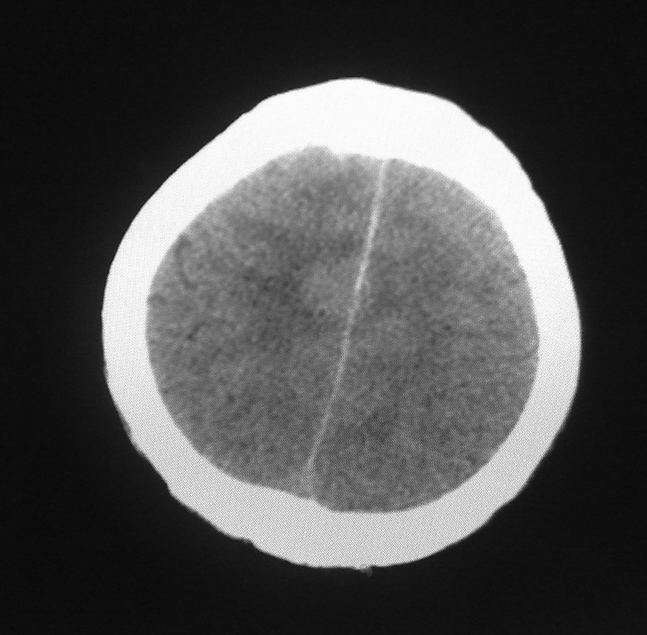

男,61岁,发热,有脑出血病史。

右侧基底节,放射冠软化灶,胼胝体发育不良 脑积水原因待查。

脑积水【脑室血块阻塞?】

脑积水!四脑室显示不清,导水管梗阻?建议mri!

右侧基底节及放射冠软化灶,脑积水,四脑室显示不清,导水管梗阻?建议mri!

梗阻性脑积水,出血后粘连所致

1)右侧基底节区、右侧放射冠及右侧丘脑软化灶。2)脑积水。